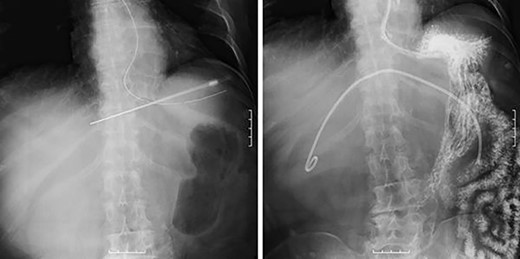

A 75-year-old bedridden woman presented to our hospital with chief complaints of epigastric pain, anorexia and a palpable mass in the epigastric region. She had a history of surgery for meningioma, but no history of abdominal surgery. Ultrasonography revealed a well-defined large cystic lesion with a long diameter of approximately 150 mm in the left liver lobe. Contrast-enhanced computed tomography showed a giant hepatic cyst with an irregular mass in liver segment 4, 20 × 16 cm in size (Fig. 1).

However, during hospitalization, the patient developed dehydration, acute renal failure, electrolyte imbalance and impaired consciousness. C-reactive protein level was elevated (9.61 mg/dL), indicating intracystic infection. As emergency treatment, percutaneous puncture drainage of the cyst was performed to decompress the stomach and duodenum (Fig. 4).

Percutaneous puncture drainage improved the obstruction of duodenum.